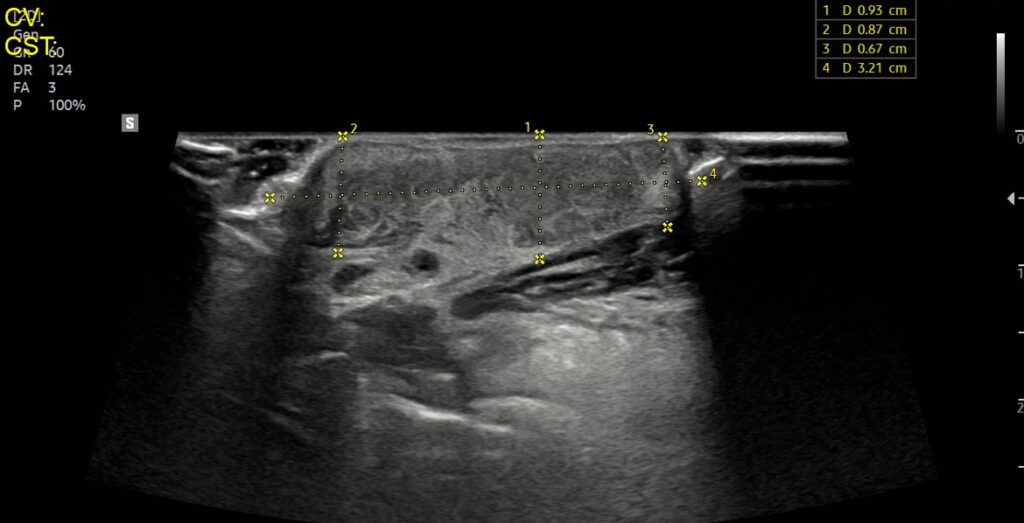

초음파 검사 결과

우측 턱밑샘 주변에서 fluid(액체) 음영이 확인되었고, 이 소견을 바탕으로 침샘낭종(sialocele) 또는 농양(abscess) 의 가능성이 고려되었습니다. 이에 따라 초음파 가이드 하 세침흡인검사(FNA, Fine Needle Aspiration) 를 진행하였으며, 혈액과 점액이 섞인 삼출물 약 1mL를 채취하여 세포학적 검사를 의뢰했습니다.